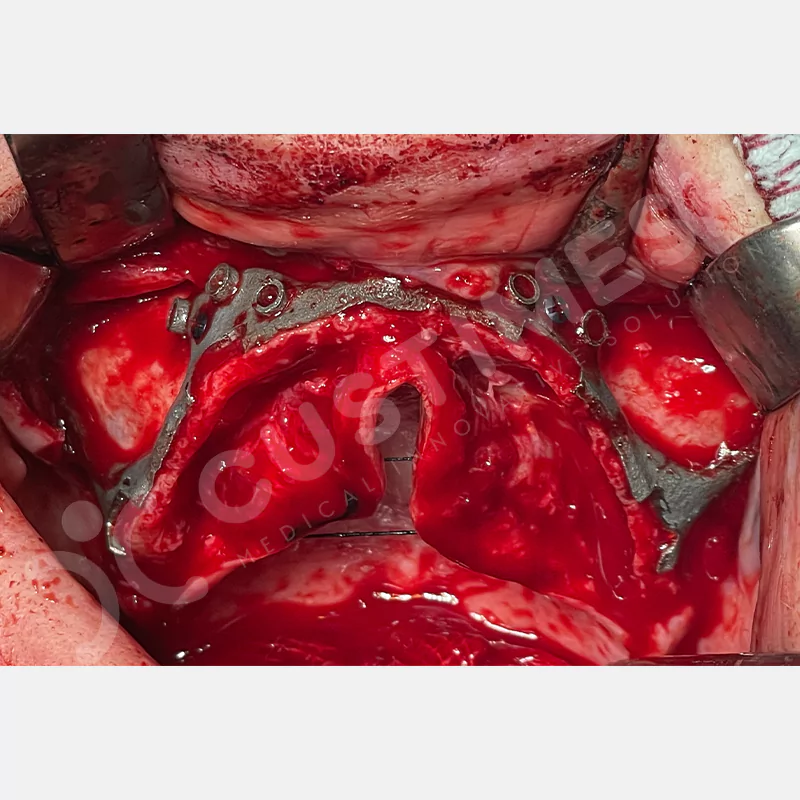

Modern diş hekimliğinde, çene gelişimini tamamlamamış veya ciddi kemik kaybı yaşayan hastalar için kişiye özel titanyum implantlar ile çözüm bulunmaktadır. CAD/CAM teknolojisi ve lazer sinterleme yöntemiyle üretilen bu implantlar, hastanın bireysel anatomik yapısına tam uyum sağlayarak geleneksel implantların uygulanamadığı vakalarda mükemmel bir alternatif oluşturmaktadır. Özellikle ileri derecede kemik kaybı olan hastalar için geliştirilen subperiosteal implantlar, periostun altına yerleştirilerek minimal invaziv bir yaklaşım sunarken, bilgisayarlı tomografi verileri ve sonlu eleman analizleriyle optimize edilmiş tasarımları sayesinde hem estetik hem de fonksiyonel sonuçlar garanti etmektedir. Bu yenilikçi teknoloji, tek seansta implant ve protez uygulamasına imkan vererek hastaların aynı gün doğal gülüşlerine kavuşmalarını sağlarken, kemik greftleme gibi ek işlem ihtiyacını ortadan kaldırarak cerrahi süreci büyük ölçüde kolaylaştırmaktadır. Kişiye özel tasarımı ve üstün biyouyumluluğu sayesinde, daha önce tedavisi mümkün görülmeyen kompleks vakalarda bile başarılı sonuçlar sunan bu implantlar, modern diş hekimliğinde yeni bir çağ açarak hastaların yaşam kalitesini artırmayı hedeflemektedir.

VAKA 1